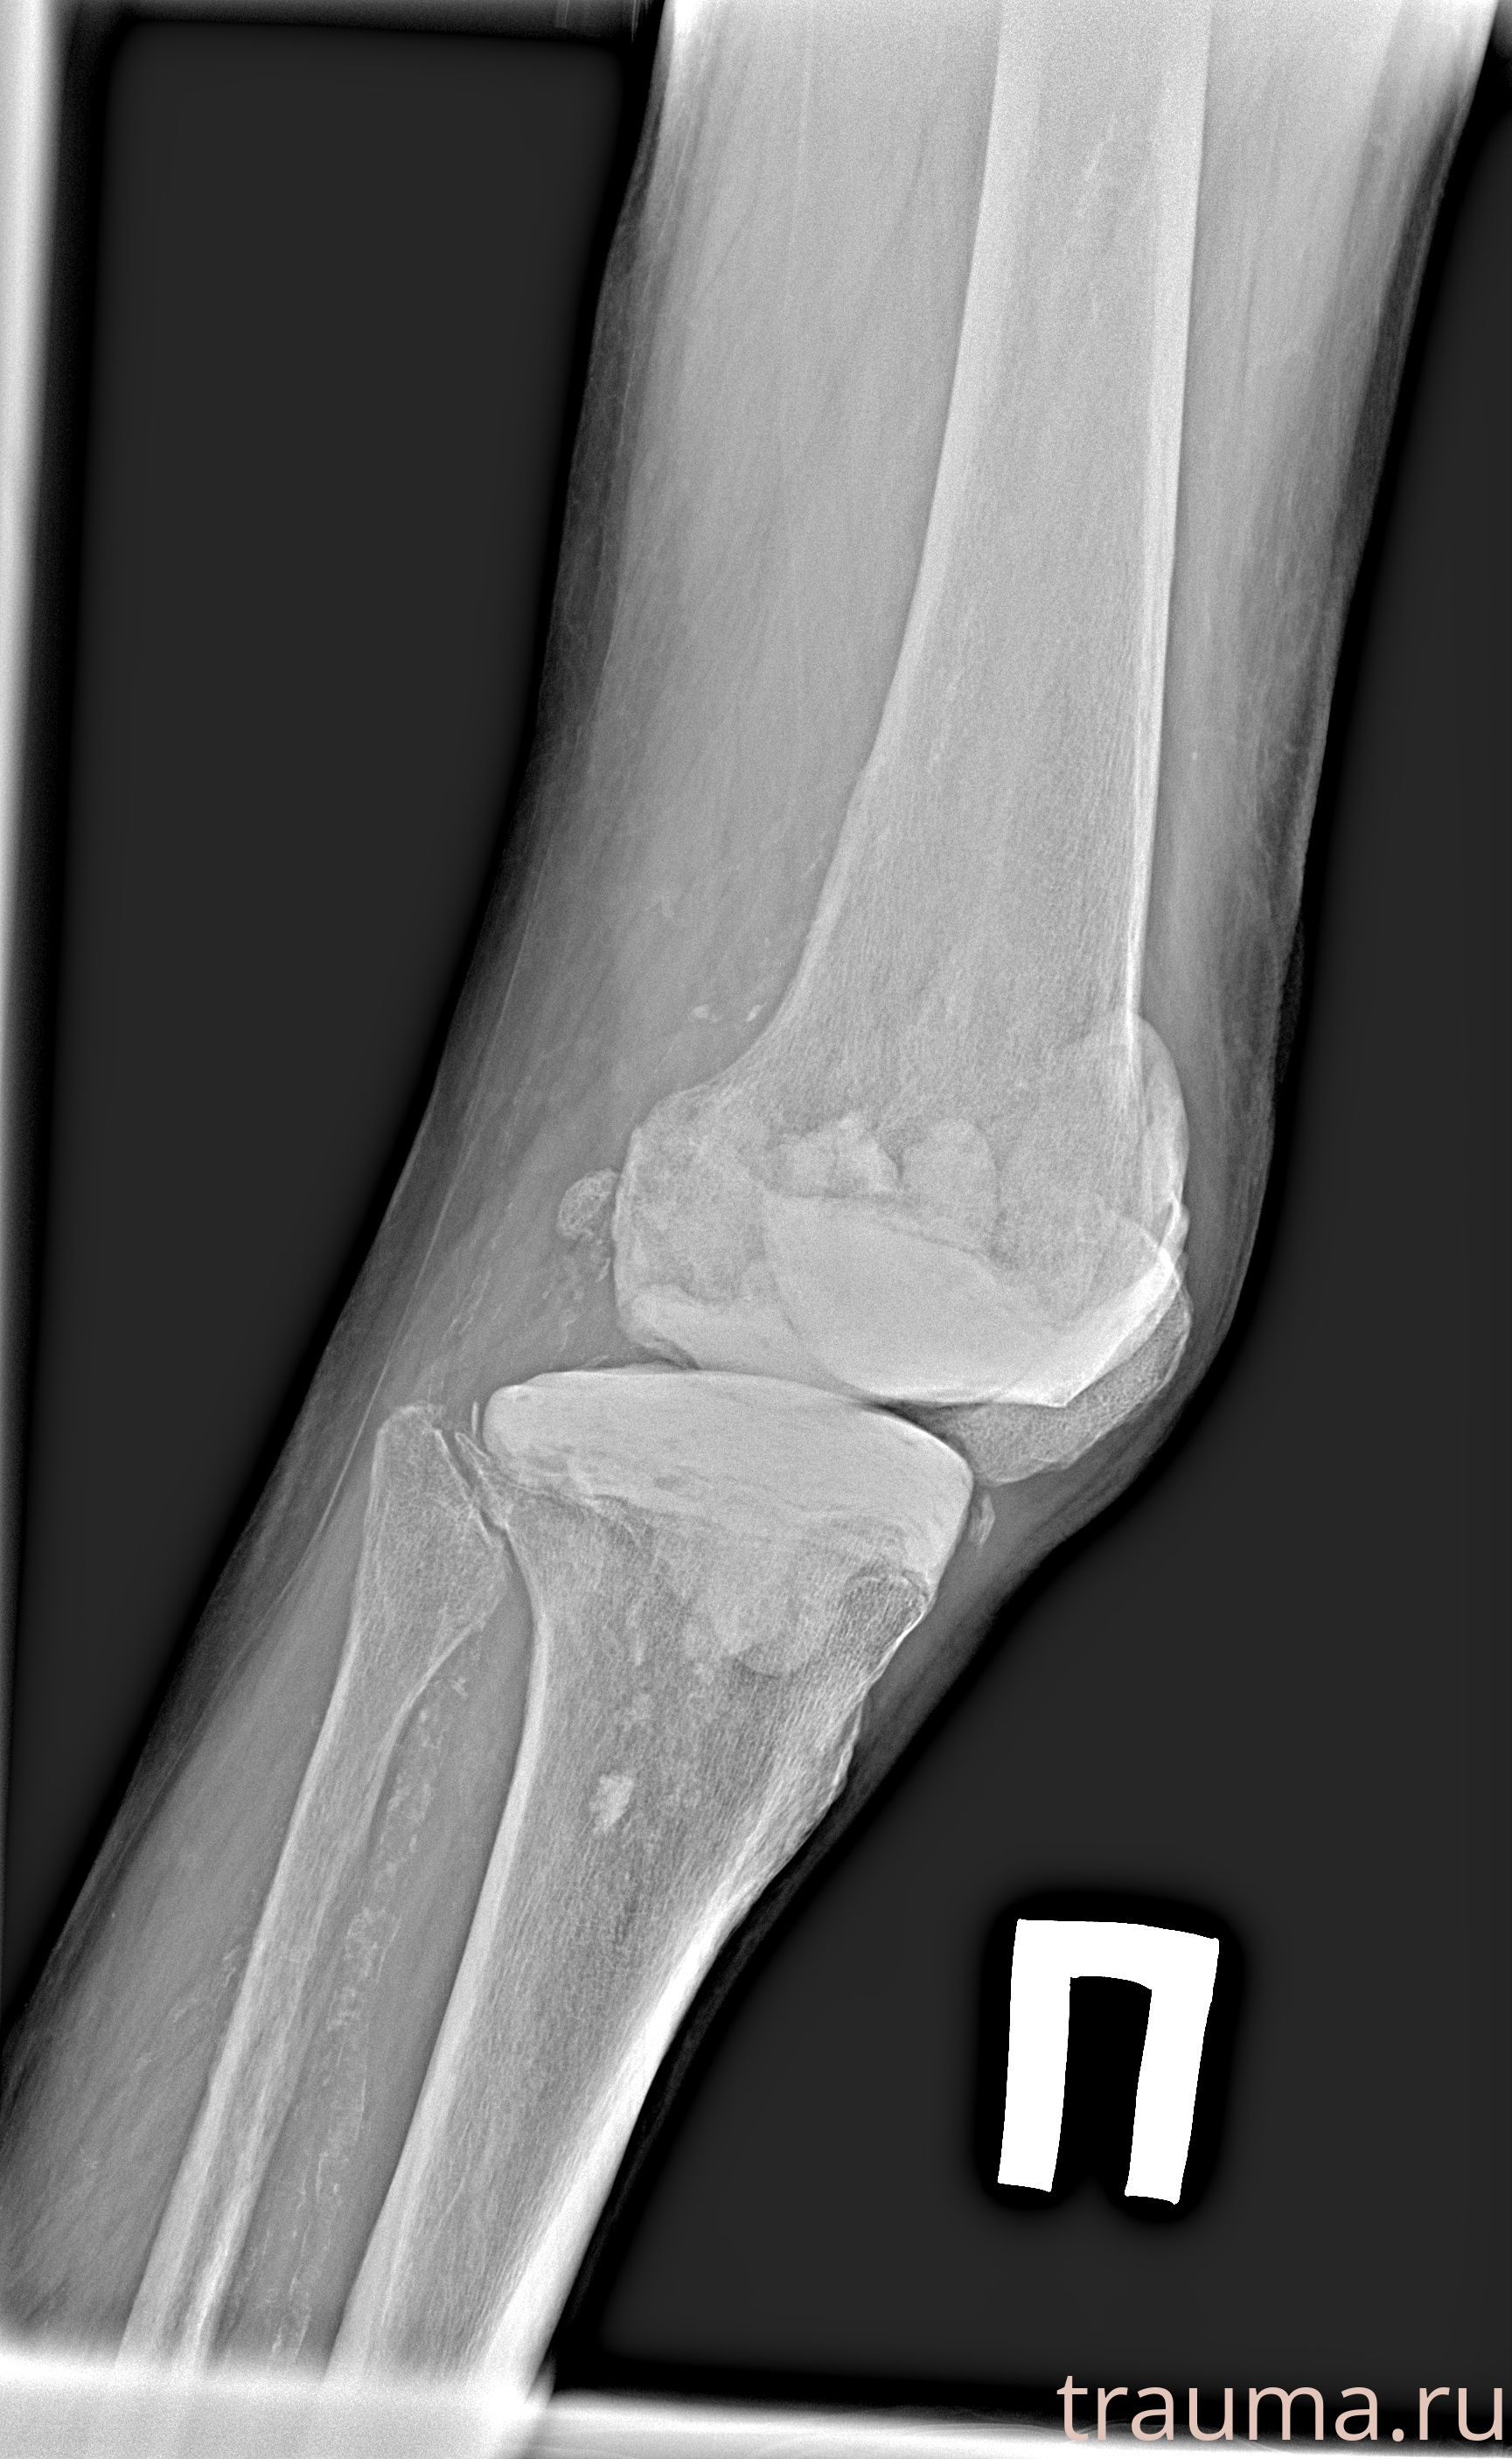

Рентгенограммы

Рентген на дому: по вашему адресу приезжает врач-рентгенолог, травматолог-ортопед с мобильным рентгеновским аппаратом, проводит диагностику травмы или заболевания, делает необходимые рентгенограммы, дает рекомендации по дальнейшему лечению. Получить качественные снимки в домашних условиях возможно благодаря уникальной методике, разработанной МосРентген Центром для института  Склифосовского